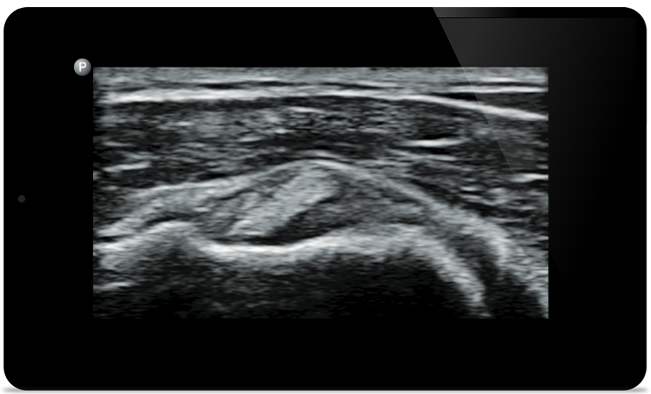

Lumify helps you see the fine details in muscles, joints, ligaments, tendons and cartilage to make a more accurate diagnosis of injuries.

Lumify can help you assess patients from head to toe, whether it’s plantar fasciitis, tendonitis or bursitis in the patellar tendon, or even shoulder instability in the rotator cuff.

Supraspinatus tendon tear